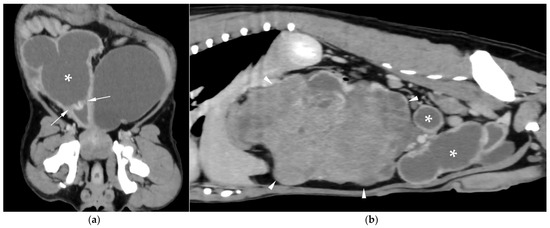

AUS in all three dogs revealed a fluid-filled cavitary structure originating in the caudal peritoneum between the colon and urinary bladder and extending cranially through the mid-abdomen, causing a mass effect. In cases 1 and 2, the lesion continued bilaterally as paired, thin tubular extensions coursing caudally through the inguinal rings adjacent to each testis (Figure 1a). In case 1, a focal mural narrowing resembling a uterine cervix was noted caudally (Figure 1b). The wall was thin and smooth in case 1, while in case 2 it was irregular, especially in its caudal aspect (Figure 2a,b). No information was available regarding the course of the UM horns or wall appearance for case 3. The luminal content consisted of echogenic, inhomogeneous fluid in all cases (Figure 3a); in case 2, sedimentation created fluid–fluid levels (Figure 3b).

Figure 1. Abdominal ultrasound (AUS) of case 1: (a) Oblique view of a uterine horn (arrowheads) within the scrotum, with the testis in the center (asterisk) and the epididymis on the right side of the image; (b) Longitudinal view of the caudal aspect of the uterus masculinus (UM) showing a focal cervix-like mural narrowing ventral to the descending colon (arrows).